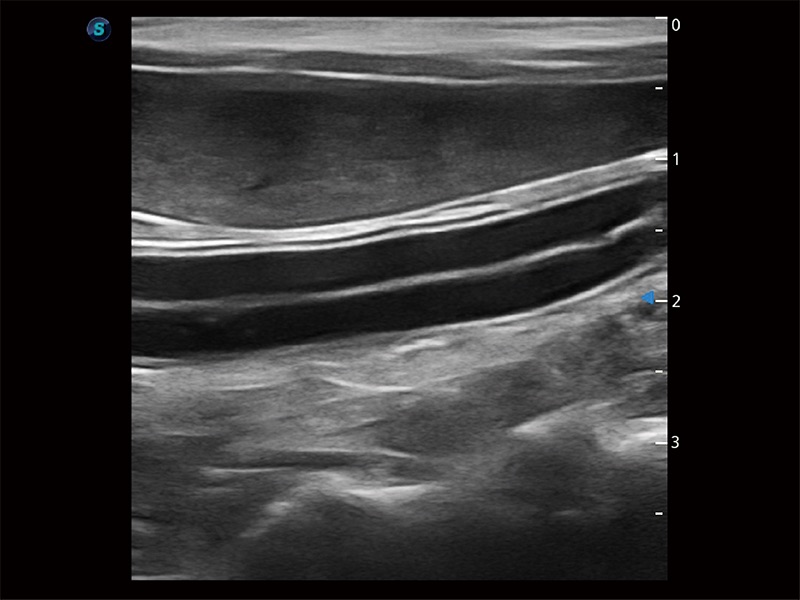

高性能和先进的临床应用工具可以为动物医生提供临床信心。ProPet 80 搭载了先进的腹部和浅表应用工具,帮助医生在日常临床实践中发挥前所未有的作用。

操作简便,无需高频度外力作用即可真实反映组织的形变,快速评估肿瘤良恶性。

为精细结构及组织边缘提供高清晰度的图像和更大的成像视野。帮助减轻医生的用眼疲劳,快速精准获得测量的数据。

ProPet 80 全新的动物超声智能软件和丰富的探头群,为动物医生提供了高清晰度和精细分辨率的图像,无论在宠物、马科、畜牧还是实验室动物等应用中都可以轻松应对,为您的日常工作带来满意的体验。